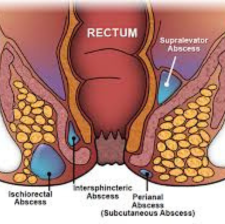

Perianal Abscess

A perianal abscess is a type of anorectal abscess that is confined to the perianal space.Other causes can include inflammatory bowel diseases such as Crohn's disease, as well as trauma, or cancerous origins. Patients with recurrent or complex abscesses should be evaluated for Crohn's.

Rectal Abscess

A collection of pus in the tissue around the anus and rectum.Anorectal abscess is usually caused by anal infection or blocked glands. It can result from sexual transmission or a disorder, such as Crohn's disease or